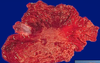

grade this disease

what does micro show?

low grade dysplasia of Barrett esophagus

crowded hyperchromatic nuclei

decreased goblet cell formation